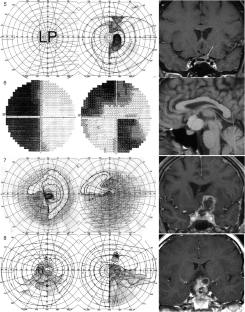

The hemi-decussation at the optic chiasm creates the potential for crossed and uncrossed fibers to be affected in isolation or in various combinations of nerve, chiasm and tract, with patterns that reflect the retinotopic arrangement of axons. We present seventeen cases that illustrate the field defects that can result and review the literature to create a taxonomy of junctional visual field defects. The complete junction defect is blindness in one eye and loss of the entire temporal field of the other. The classic junctional scotoma combines optic neuropathy in one eye with upper temporal hemifield loss in the other, and is often a sign of ventral compression. The less frequent atypical junctional scotoma involves the lower temporal hemifield and has a higher frequency of dorsal compression or non-compressive pathology. There are the monocular defects in the temporal (‘junctional scotoma of Traquair’) or nasal hemifield, the latter of which is rarely if ever due to a pituitary adenoma. Highly asymmetric bitemporal defects with or without a central scotoma and the paradoxical junctional scotoma occur by extension of the lesion causing the junctional scotoma of Traquair. The posterior junction defect results from combined damage to the optic chiasm and optic tract. Recognizing these various patterns is important clinically as junctional defects have the same localizing significance as bitemporal defects and are being encountered more often. In addition the probability of certain types of pathology varies with the type of junctional defect.

Figures in cases 1, 6 and 12 are adapted with permission from: Barton JJS, Benatar M. Field of Vision: a manual and atlas of perimetry, Humana Press (now Springer Nature), Totowa NJ, 2003, and those of cases 7, 9 and 15 are reproduced with permission from www.neuro-ophthalmology.ca. We thank Briar Sexton for sharing case 9 with us.

Barton, J.J.S., Özturan, G. The varieties of junctional scotoma: 17 cases, a review, and a taxonomy. Eye 39, 1673–1687 (2025). https://doi.org/10.1038/s41433-025-03789-z